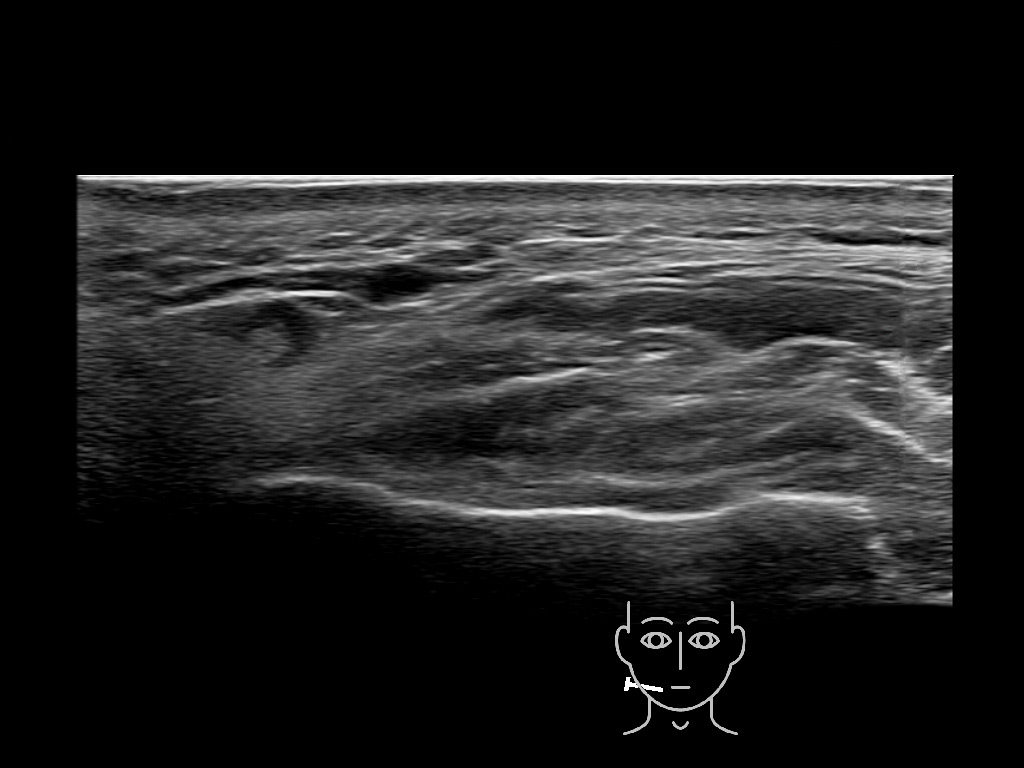

Filler deposits may end up unintentionally in the SMAS or fascial layers of the skin. Very often this will not lead to adverse events, however, adverse events ( nodules, migration / redistribution impaired muscle movement and smiling and malar edema) are are often related to filler ending up in the SMAS or fascia.

Study the first image to recognize the different layers. If you are sure about the layers, swipe to the second image to view the answer (if applicable).